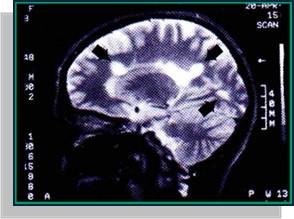

A confirmação da doença faz-se geralmente por exclusão de todos os outros possíveis estados. Um neurologista pode realizar testes para ajudar a confirmar o diagnóstico, incluindo punções lombares, registos da actividade eléctrica do cérebro, tomografia axial computorizada (TAC) e tomografia por ressonância magnética (RMN) que é a mais utilizada.

A ressonância magnética (RM) é a técnica de imagem mais precisa para o diagnóstico, dado que pode revelar a presença de áreas do cérebro que perderam a mielina. A RM pode inclusive distinguir áreas de desmielinização activas e recentes de outras mais antigas que se produziram à tempos atrás.

O diagnóstico não é simples e pode levar alguns anos para ser feito correctamente, pois os sintomas assemelham-se, em alguns casos, com outros tipos de doenças do sistema.

Figura 4 - Ressonância Magnética (RM)